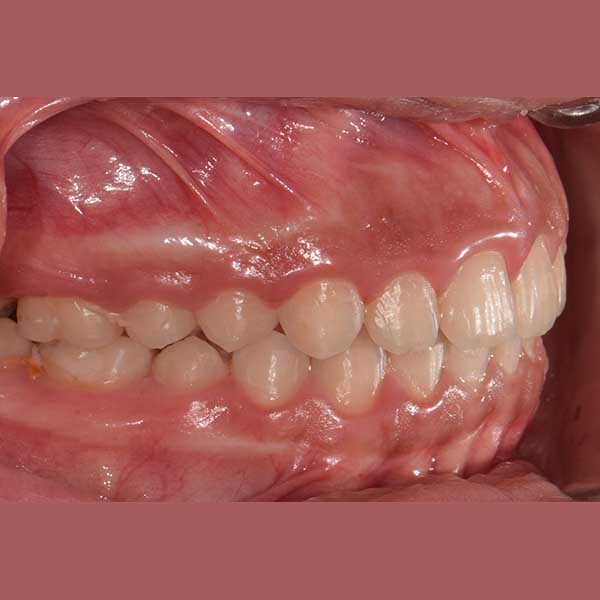

AFTER

Protruded upper anteriors – fixed metal braces

This little girl has visited me with her mother, she was suffering from the protrusion of her front teeth, which affected her psyche and smile; in addition to its negative impact on her pronunciation

After examining the case, I found that the upper of her front teeth were 8 mm of her lower front teeth, which is a large distance (normal to be 1 to 2 mm). The parents refused the option of tooth extraction, because of her young age, so I solved the problem without extraction because the main problem was caused by the retraction of the lower jaw I fixed it simply with a functional device

At the end of the treatment, the problem of the eruption was corrected and our friend has got back her smile with confidence again.